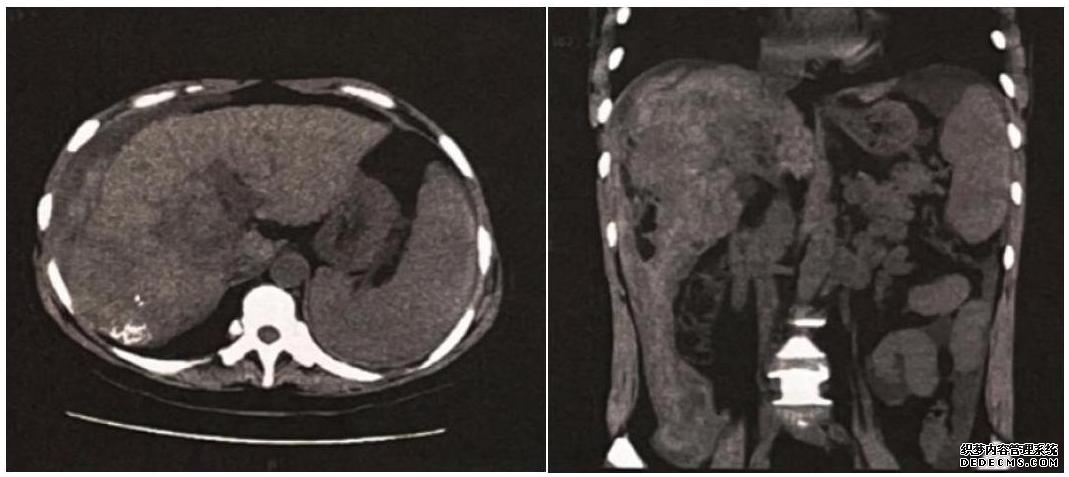

(2)影像学检查:腹部CT(增强,2022年3月12日)示肝癌介入术后改变,病灶残余,新发灶不除外,门脉右支及肝门区胆管受侵,肝硬化伴多发再生结节形成,腹水。腹部CT(平扫,2022年3月17日):肝右叶肝癌破裂出血,腹水量较前增加(图1)。腹部CT(平扫,2022年3月26日):肝癌介入术后改变,腹腔及盆腔积液,腹腔内血肿较前吸收(图2)。

图1

该患者为肝硬化基础上发生的肝癌,影像学提示门脉右支及肝门区胆管受侵,患者突发腹部疼痛,血压下降,既往有肝脏肿瘤破裂史,排除宫外孕,急诊腹部CT提示肝右叶肝癌破裂出血,即予肝动脉栓塞,出血控制,救治成功。